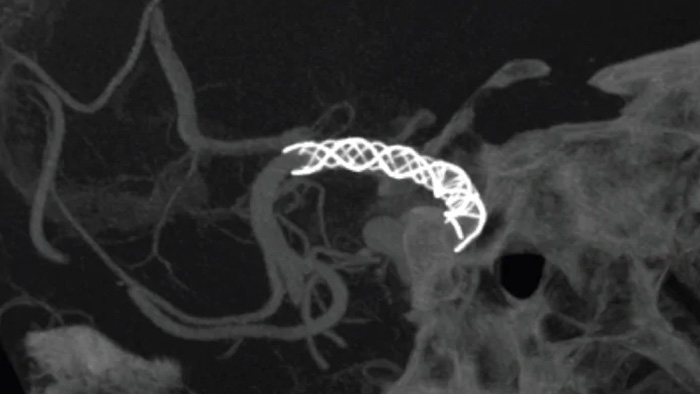

SmartCT Vasoを使用すると、血管内ステント、フローダイバータ、その他のデバイスの視認性が向上するだけでなく、血管の形態を穿通枝レベルまで詳細に確認できます。この画像取得技術は、コーンビームCTスキャンと動脈内造影注入に基づいています。この手法はフローダイバータ、その他のデバイスの視認性が向上するだけでなく、血管の形態を穿通枝レベルまで詳細に確認できます。この画像取得技術は、コーンビームCTスキャンと動脈内造影注入に基づいています。この手法はフローダイバータステントで治療した動脈瘤の追跡検査に使用されるケースが増えています。